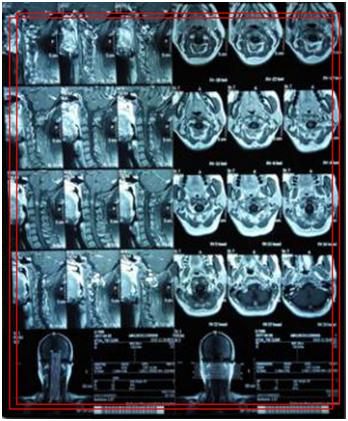

(颈段海绵状血管瘤)